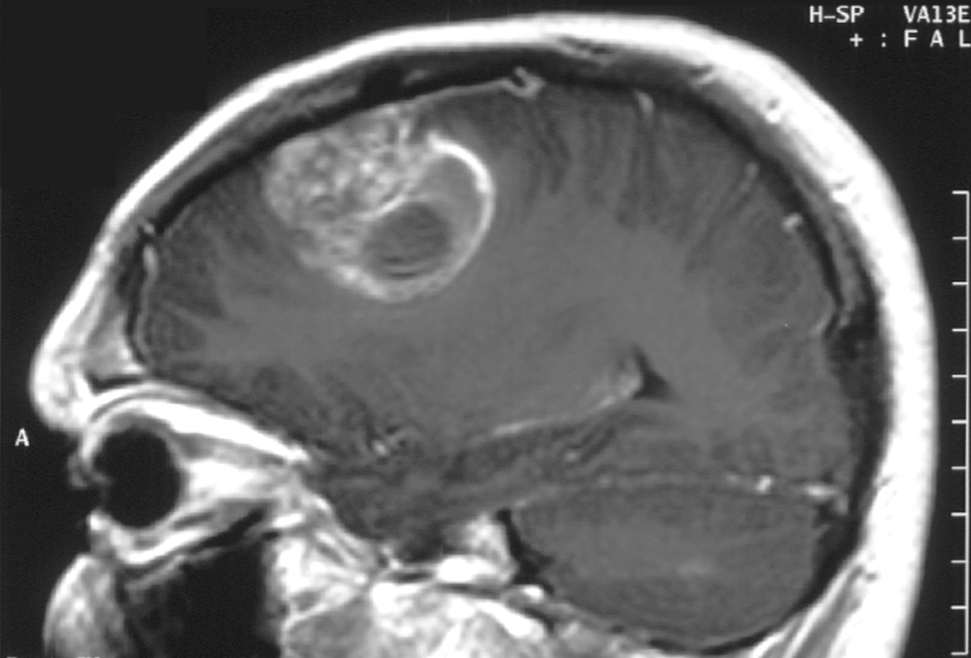

Although not yet reviewed by regulators, Glaxo's shingles vaccine also performed well. Combined royalties from both programs could give Agenus the capital it needs to advance its wholly owned Prophage vaccine program in brain cancer. This is a unique process that involves extracting proteins from a patient's tumor, which involves brain surgery. The proteins are shocked with high temperatures to create an individualized vaccine.

Multiforme glioblastoma is one of the deadliest malignancies around. Left untreated, patients uniformly die within three months. Even with the best available treatments, about half don't last a year, and the two-year survival rate is a dismal 25%.

Roughly 10,000 Americans are diagnosed with these aggressive brain tumors each year. Luckily, results from an open-label phase 2 trial suggest Agenus' fully owned Prophage treatment can greatly improve chances of long-term survival. Last summer, Agenus announced that 50% of the 46 newly diagnosed glioblastoma multiforme patients given Prophage along with radiation and chemotherapy were still alive after two years.

Basically doubling patients' chances of surviving two years is incredible, but it gets better. This summer, Agenus split these patients into two groups based on how much PD-L1 is on the surface of their white blood cells. This is an immune checkpoint receptor that tumors exploit to hide from the immune system. It was 27 months before half of the patients in the lower PD-L1 group experienced a worsening of the disease. It was 44.7 months before half these patients died, and six made it past 38 months. A vast improvement over standard of care in the higher PD-L1 group was also observed, but it was hardly as pronounced.